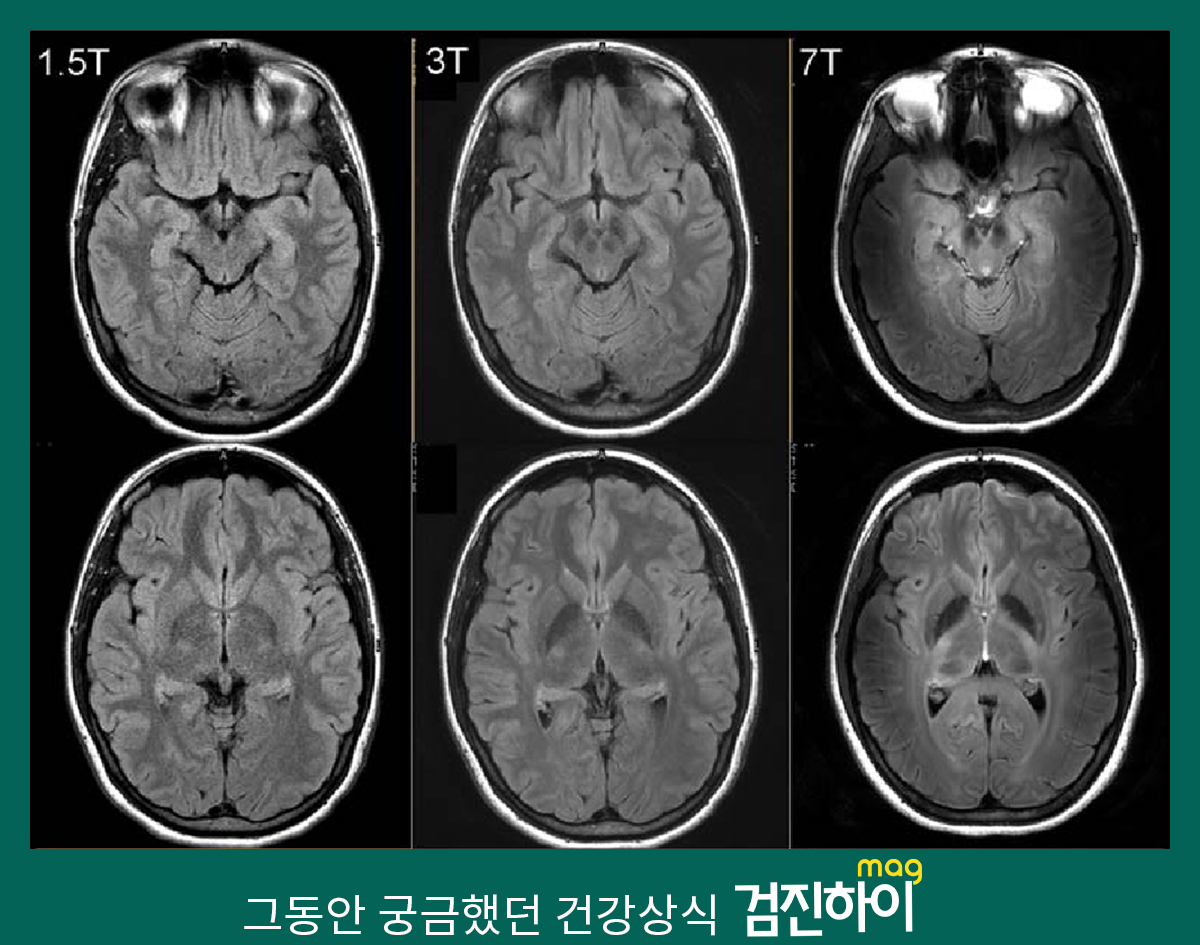

MRI 기계의 성능은 테슬라(Tesla) 수치에 따라 달라집니다. 테슬라 수치가 높을수록 더 정밀한 이미지를 제공하며, 다양한 질환을 진단하는 데 유리합니다.

아래의 표는 테슬라 수치에 따른 치료 가능 부분을 정리한 것입니다.

| 테슬라 수치 | 치료 가능 부분 |

| 1.5T | 뇌, 척추, 관절 질환 |

| 3.0T | 심장, 혈관, 종양 진단 |

| 7.0T | 연구용, 고급 진단 |

일반적으로 1.5T와 3.0T MRI 기계가 많이 사용되며, 7.0T는 연구 목적으로 사용됩니다.